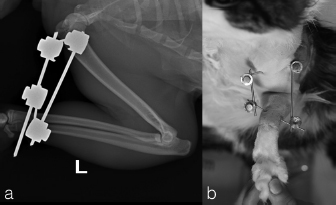

Two, spayed, Domestic Shorthaired cats with an age of 1.5 years (case 1) and 6 years (case 2) were referred to the author’s clinic for the non-weight bearing left forelimb lameness after a suspected trauma. Physical examination, of both cats, revealed moderately swollen and painful left elbow, with abnormal posture characterized by extended rotation of antebrachium and supination of the paw. Orthogonal radiographs of forelimbs demonstrated a complete caudal elbow luxation (Fig. 1). The radius and ulna were caudally and proximally displaced in relation to the humerus; furthermore, in case 1, a small avulsion bone fragment (2 mm diameter) closed to the lateral aspect of the humeral condyle was presented. No other abnormality was identified during the physical and radiographic examinations. The cats were sedated by intramuscular administration of dexmedetomidine (Dexdomitor: Pfizer Italia Srl, Rome, Italy) (10 μg/kg) and methadone (Semfortan: Dechra Veterinary Products Srl, Turin Italy) (0.4 mg/kg). General anesthesia was induced with propofol (Proposure: Merial Italia Spa, Milan, Italy) (6 mg/kg) intravenously and, after oro-tracheal intubation, maintained with isoflurane (IsoFlo: Aesica Queenborough Limited, Kent, United Kingdom) and oxygen. Modified closed reduction technique was attempted in both cases. Distal traction of antebrachium with full extension of the elbow was initially achieved followed by simultaneously applying distal pressure on the olecranon and partial elbow flexion. Following successful reduction, the collateral ligaments integrity was indirectly assessed with the Campbell’s test (1971), with normal limits value around 110° of supination and 70° of pronation recorded in both patients. The joint stability and reduction were maintained with gentle manipulation. However, instability was present at 100° of elbow extension, while major stability was obtained at 40° of flexion. For this reason, the elbow was held at 40° of flexion and a simple transarticular external skeletal fixator type IIa was applied to maintain the stability of the joint. Due to the forced flexion position, which limited the biomechanics movement, the cats were not able to weight bearing in the postoperative period. Two full pins, smooth Kirschner wires 2.0 mm of diameterf were inserted in the proximal third of the diaphysis of the humerus and in the distal third of the radial diaphysis. Stainless steel connecting bars (Gènia. St. Hilaire de Chaléons, France) (3.0 mm) were positioned medially and laterally connecting with Maynard clamps (Gènia. St. Hilaire de Chaléons, France) to the full pins (Fig. 2). The avulsion bone fragment was not treated in case 1. The patients were discharged from the clinic 24 hours after surgery. Cage rest without any exercise was recommended for 2 weeks and meloxicam (Meloxoral: Fatro S.p.A., Ozzano Emilia, Italy) (0.05 mg/kg) was administrated for 7 days.

Fig. 2. Transarticular external skeletal fixator type IIa applied to maintain the stability of the joint (case 1).